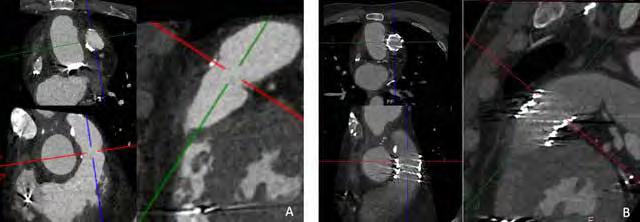

The activities of the MR Physics group are driven by clinical research lines of the Radiology and Nuclear Medicine department such as musculoskeletal research (with Edwin Oei), Lung MRI (with Harm Tiddens and Pier Luigi Ciet) and neuro-oncology (with Marion Smits). Besides the clinical research lines, it is important to notice that several fruitful projects are carried out on technical developments.